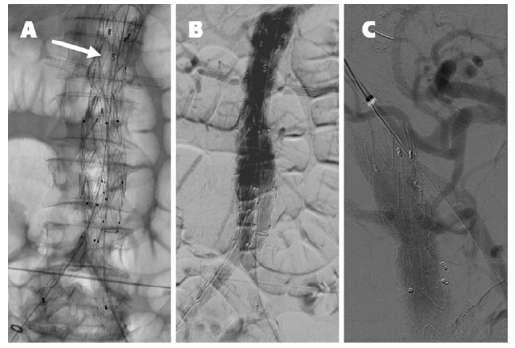

A 30 mm thoracic aortic endograft platform (Valiant Captivia, Medtronic®) was deployed with renal fenestrations positioned at 3 and 9 o’clock (Figure 1), crafted with thermocautery. The modifications were reinforced with pushable coils and secured with a continuous polypropylene suture (Video 1). To facilitate precise orientation upon implantation, one of the endograft’s proximal radiopaque markers was reshaped into an ‘S’ configuration and re-implanted on the graft’s anterior aspect (Figure 2, arrow on panel A). No diameter-reducing ties were employed. The graft was re-sheathed using a strangling silk technique (Video 2). PMEG preparation was completed within 90 minutes.

Although not seen, the superior mesenteric artery is patent. The arrow on panel A indicates the ‘S’ shape radiopaque marker implanted on the anterior aspect of the graft for position reference. Panel C shows the completion angiography after the balloon-expandable stent graft deployed via the upper-arm approach in the superior mesenteric artery.

Standard EVAR techniques facilitated the distal bi-iliac repair (36 mm main body, Endurant IIs, Medtronic®). A completion aortogram was performed at the end of the procedure (Figure 2, panel B), which was completed in 145 minutes, involving the administration of 120 mL of contrast and a cumulative fluoroscopy time of 78 minutes. Control CTA on the following day identified partial occlusion of the superior mesenteric artery ostium caused by the graft scallop. This issue was resolved via an upper-arm approach by deploying an 8 mm balloon-expandable endograft (Viabahn VBX, Gore Medical®) (Figure 2, panel C).